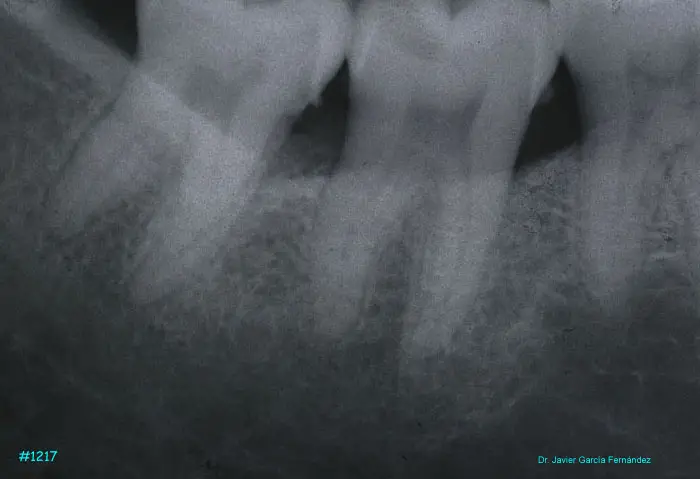

Atlas of Surgical Techniques in Periodontics. Chapter III. Atlas de Técnicas Quirúrgicas en Periodoncia

image467